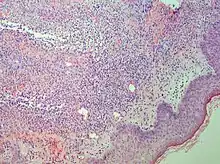

| Secondary syphilis | Various, but often one or a combination of:[21]

|

![]() |